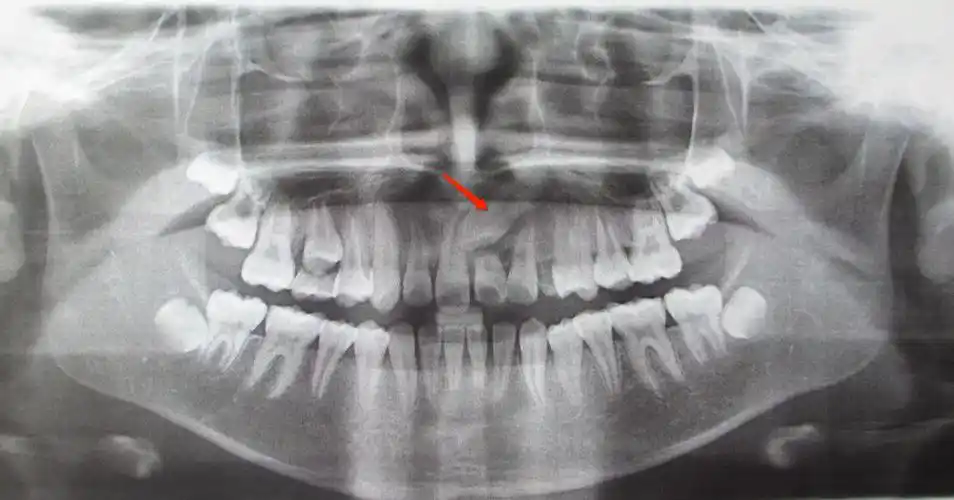

淘气的新牙,又长歪了,为什么你总不走寻常路?-郑梅钗主治医师-爱问医